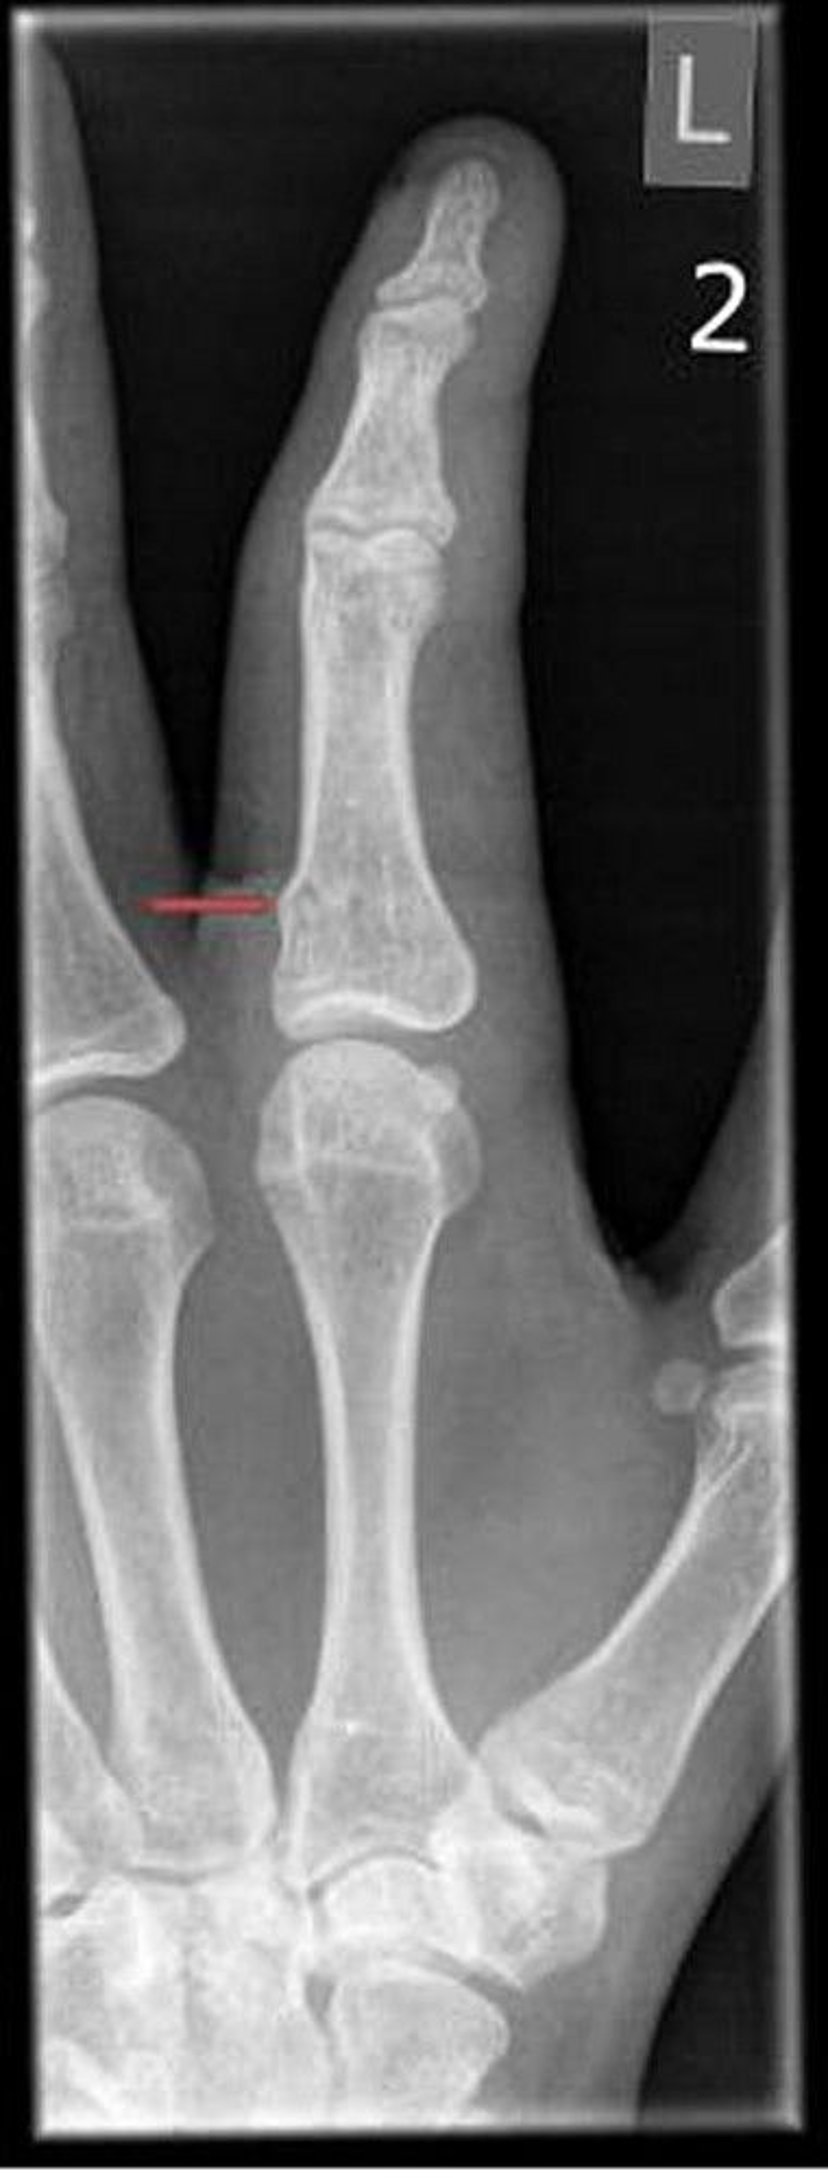

Torus Fracture of the Finger

Torus fractures may be visible only as subtle irregularities in bone cortex.